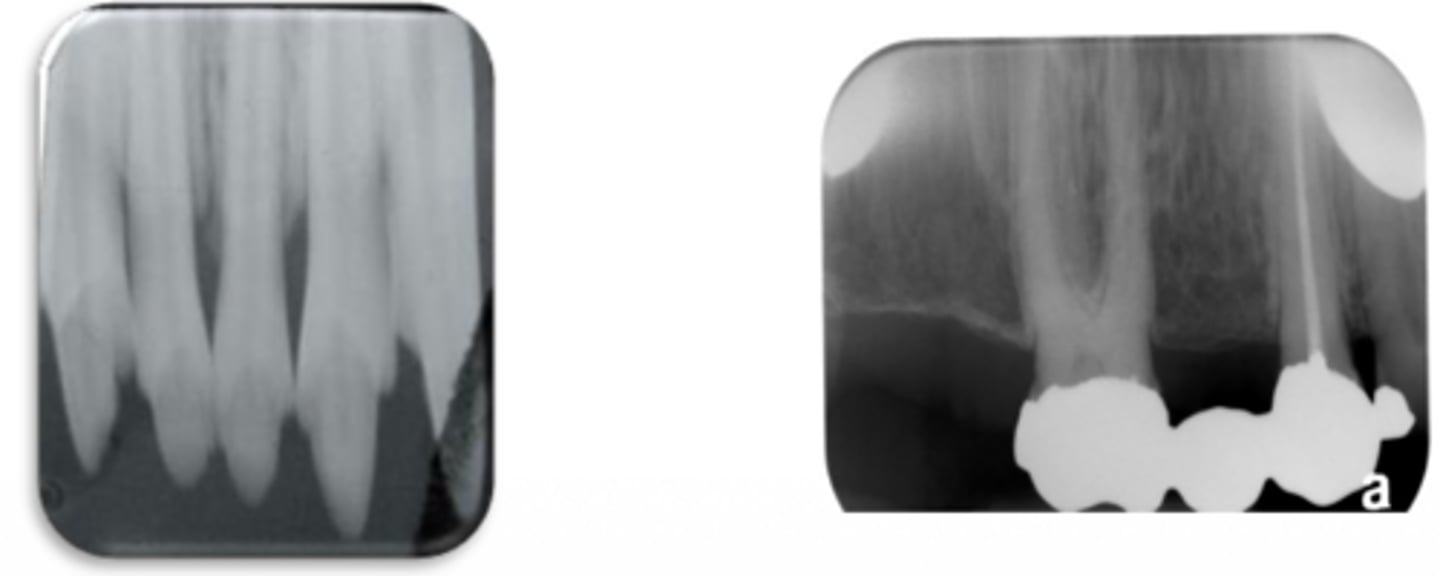

This photo was taken with the bisecting angle technique. What went wrong?

Vertical angulation is excessive --> Foreshortened image

Insufficient vertical angulation --> Elongated image